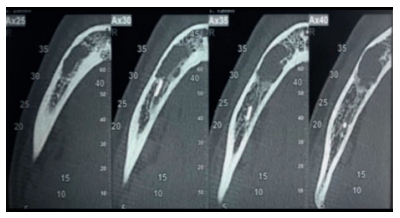

Se solicitó como prueba complementaria un CBCT mandibular. En los cortes panorámico, axiales y ortorradiales, se corroboró la presencia de lesión radiotransparente delimitada de contorno algo irregular y que no provocaba expansión de corticales (Figuras 1-4).